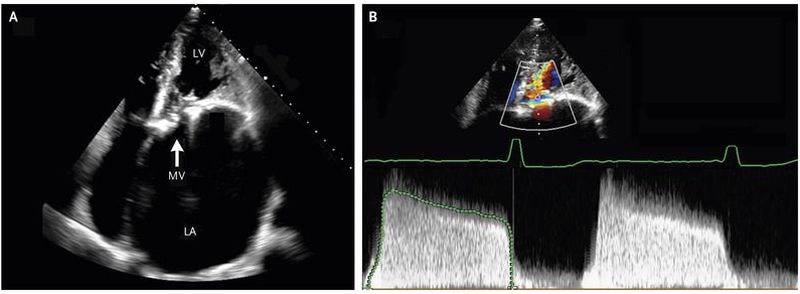

A 47-year-old man presented to the emergency department with a 6-month history of worsening exertional dyspnea. He had recently emigrated from Honduras and had a history of cardiac surgery as a child, but the initial diagnosis and specific procedure that had been performed were not known. The physical examination revealed a right parasternal heave, a loud S1, a midpeaking systolic ejection murmur (grade 2/6) at the upper sternal border, and a low-pitched diastolic rumble at the apex. An electrocardiogram showed atrial flutter with variable atrioventricular conduction. Transthoracic echocardiography revealed moderate aortic stenosis (calculated valve area, 1.3 cm2) and very severe mitral stenosis (calculated valve area, 0.5 cm2) ( Panel A; LA denotes left atrium, LV left ventricle, and MV mitral valve). The left atrium was enlarged, with an indexed atrial volume of 364 ml per square meter (normal value, <35). Color-flow Doppler images (Panel B, upper half) and a continuous-wave Doppler flow pattern (Panel B, lower half) showed the stenotic mitral valve during diastole. The continuous-wave Doppler flow pattern depicts flow velocity (vertical axis) and time (horizontal axis). The slow decline in transmitral flow velocity reflects the very slow decrease in left atrial pressure and slow increase in left ventricular diastolic pressure that occur in mitral stenosis. The mean transmitral gradient was 14 mm Hg (normal value, <3). The patient underwent replacement of the mitral and aortic valves with mechanical prostheses. At a 6-month follow-up visit, he had only slight limitations on physical activity (New York Heart Association class II).